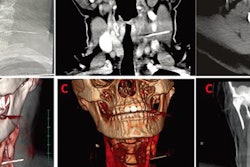

An intraoperative portable CT scan is being performed after open reduction of a facial fracture. Upon satisfactory reduction, confirmed by the scan, incisions are closed and no further imaging is necessary. If the scan shows a need for modification of the reduction or facial implant, adjustments are made at that time. No postoperative imaging is required. All images courtesy of Dr. David Shaye.Between 2012 and 2014, the group performed 38 procedures at the two centers using intraoperative CT on 30 men (79%) and eight women (21%), who had a mean age of 37.4 years (± 16 years). Each case was labeled as routine or complex.